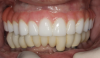

(13.) Prosthetic design allowing access to FMG interface.

Figure 13

(14.) Healthy Gingival Tissue.

Figure 14

(15.) FMG access and convex intaglio profile.

Figure 15

(16.) FMG access and convex intaglio profile.

Figure 16

Many factors should be considered when designing implant-supported restorations to reduce the risk of peri-implantitis affecting physical removal of bacterial plaque at the FMG. Included are oral hygiene devices, accessibility, prosthetic shapes, and patient ability to comply with oral hygiene procedures. The design should be conveniently hygienic so patients can easily comply with the recommended oral hygiene procedures. Physical removal of bacterial plaque on the intaglio surface at and above the FMG reduces the risk of peri-implantitis in the sub-gingival transmucosal tissue around dental implants. The original fixed prosthetic design presented by Branemark, a "High water design", provided access to all surfaces for oral hygiene management without a patient complaint of food accumulation (Figure 9 and Figure 10). Notably, relief above the gingiva was not patient complaint with this design. Lack of embrasure access to the FMG and intaglio surfaces for oral hygiene management can lead to peri-implantitis (Figure 11 and Figure 12). Stein recommended a convex modified ridgelap pontic design with lingual and palatal access to facilitate plaque removal from the intaglio surface under pontics in fixed prosthetics with dental floss.20 These shapes should be standard for fixed implant-supported restorations whether individual or multi-unit restorations made of ceramo-metal or milled zirconia (Figure 13 through Figure 16).